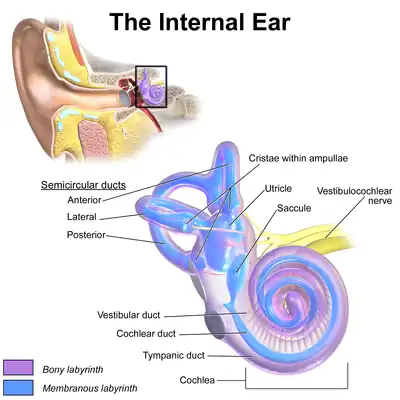

Inner ear

The inner ear sits within the temporal bone in a complex cavity called the bony labyrinth. A central area known as the vestibule contains two small fluid-filled recesses, the utricle and saccule. These connect to the semicircular canals and the cochlea. There are three semicircular canals angled at right angles to each other which are responsible for dynamic balance. The cochlea is a spiral shell-shaped organ responsible for the sense of hearing. These structures together create the membranous labyrinth.[12]

The bony labyrinth refers to the bony compartment which contains the membranous labyrinth, contained within the temporal bone. The inner ear structurally begins at the oval window, which receives vibrations from the incus of the middle ear. Vibrations are transmitted into the inner ear into a fluid called endolymph, which fills the membranous labyrinth. The endolymph is situated in two vestibules, the utricle and saccule, and eventually transmits to the cochlea, a spiral-shaped structure. The cochlea consists of three fluid-filled spaces: the vestibular duct, the cochlear duct, and the tympanic duct.[7] Hair cells responsible for transduction—changing mechanical changes into electrical stimuli are present in the organ of Corti in the cochlea.[12]